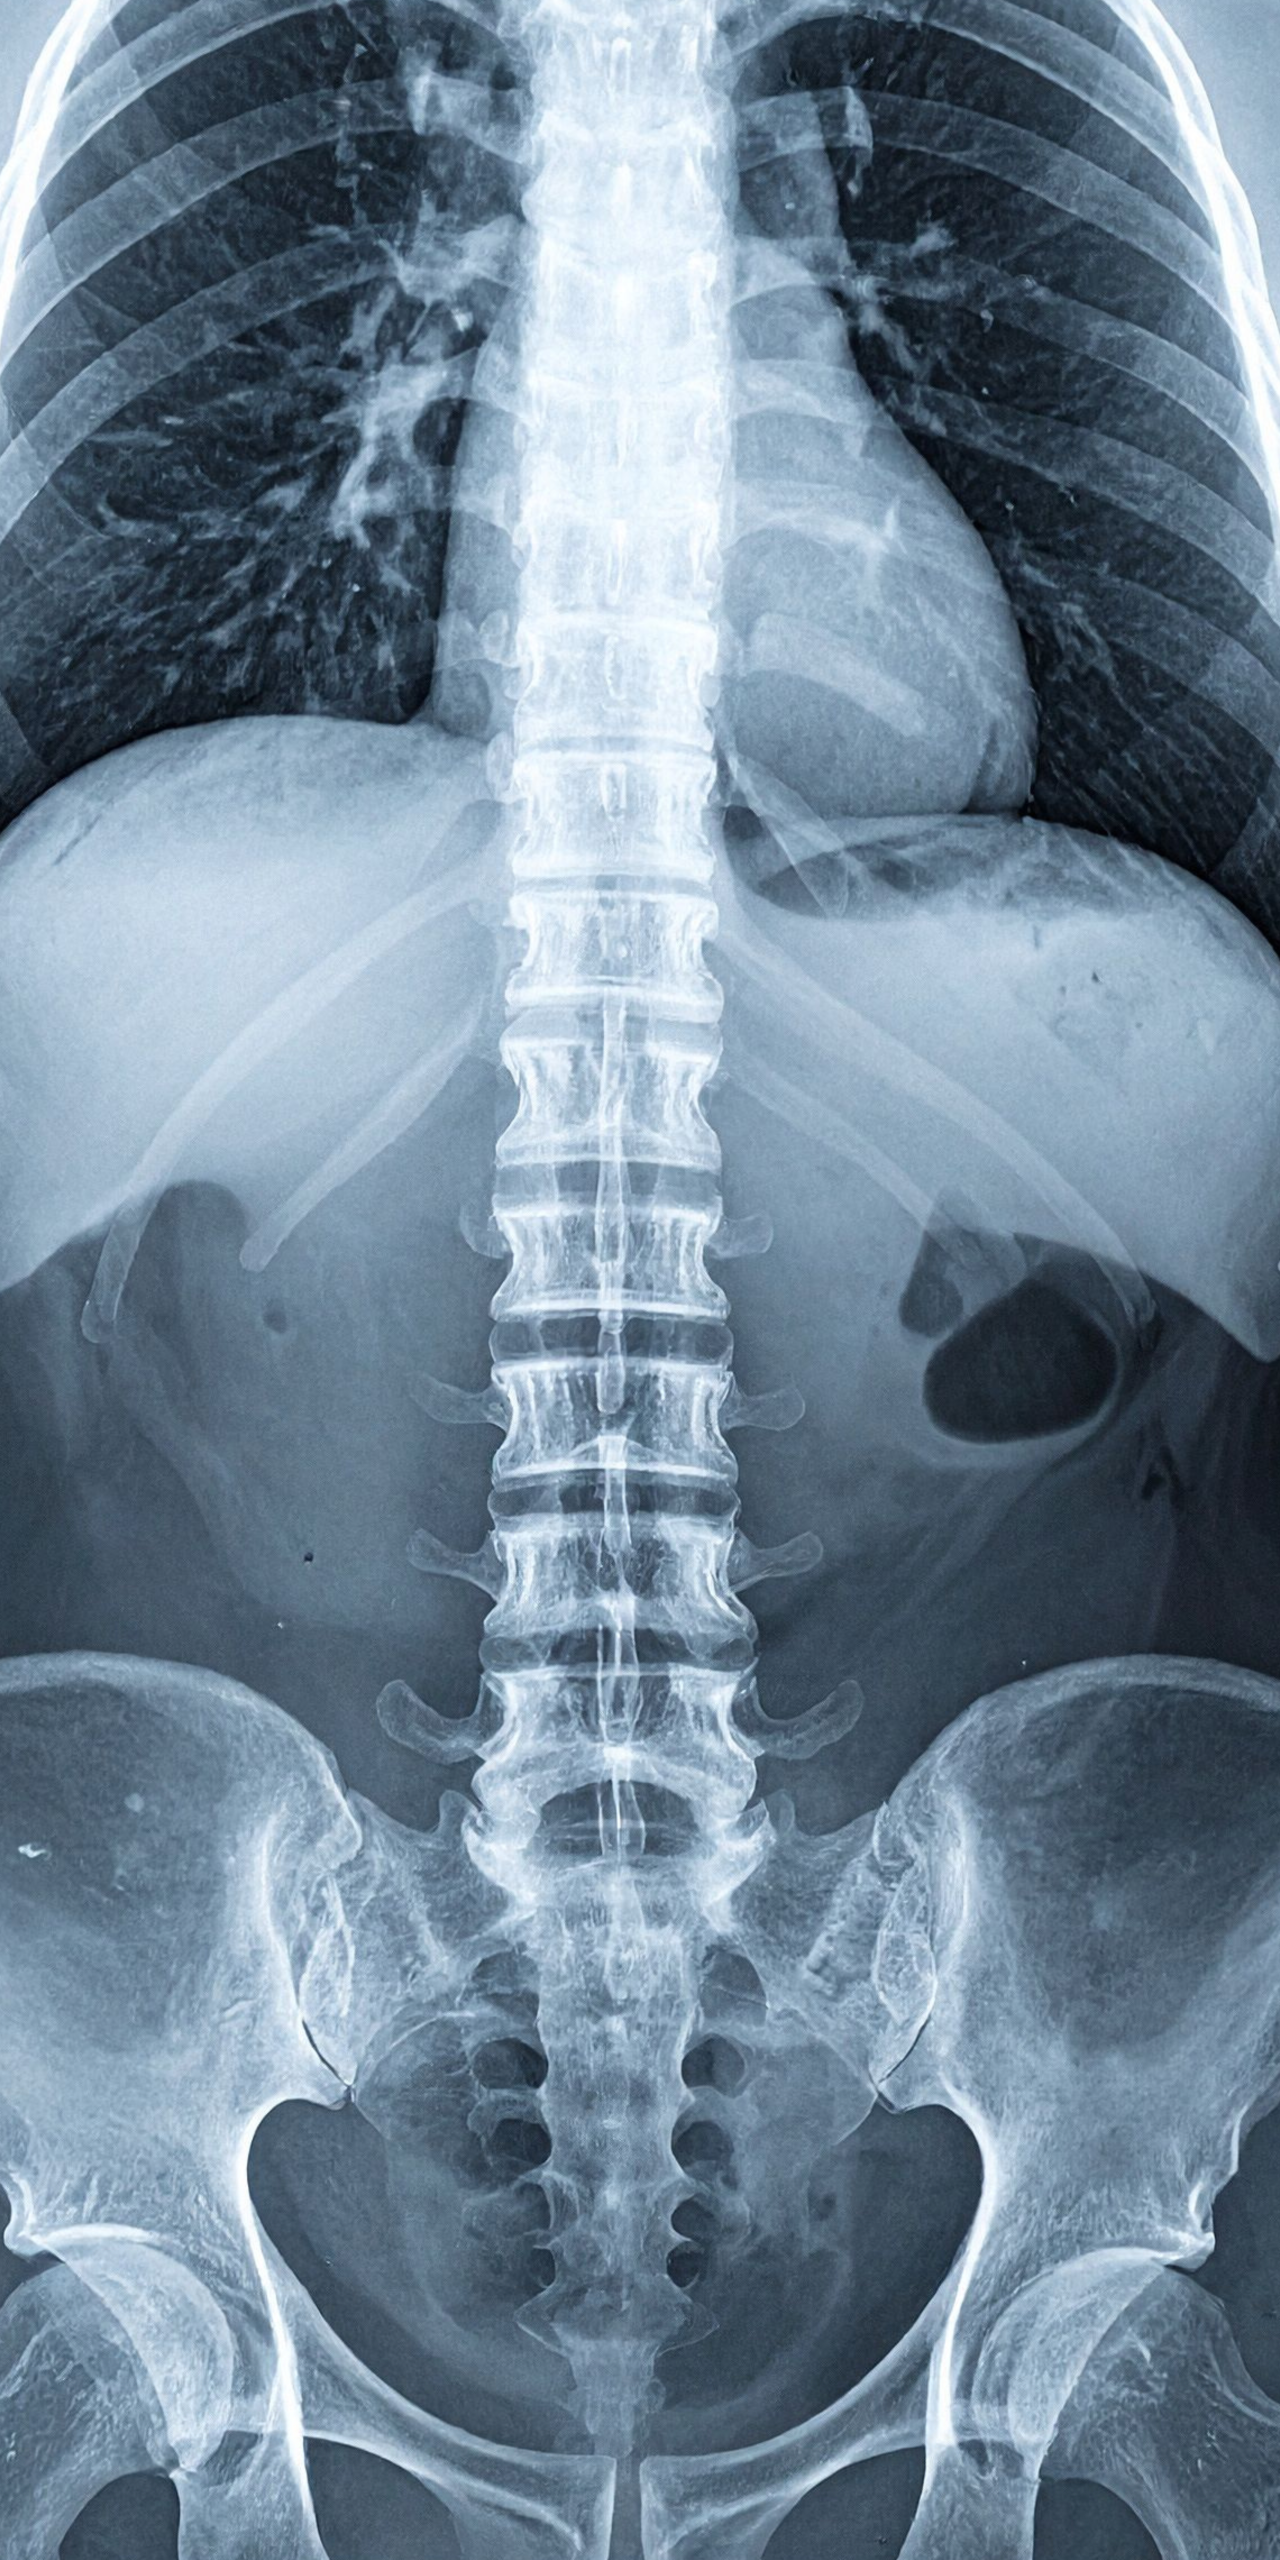

Radiografie:

• Ce poți evalua: aliniament, scolioză, cifoze/lordoze, spondilolistezis

• Când este utilă radiografia dinamică (flexie–extensie)

Lecția 7 – Scolioza: structură, rotație și implicații funcționale

• Scolioza idiopatică

• Scolioza degenerativă la adult

• Unghiul Cobb (explicat practic)

• Rotația vertebrală

• Deformările compensatorii

• Diferența între scolioză structurală și atitudine scoliotică

• Când există risc neurologic asociat

Obiectiv: să înțelegi când deformarea este doar posturală și când este structurală cu implicații mecanice reale.